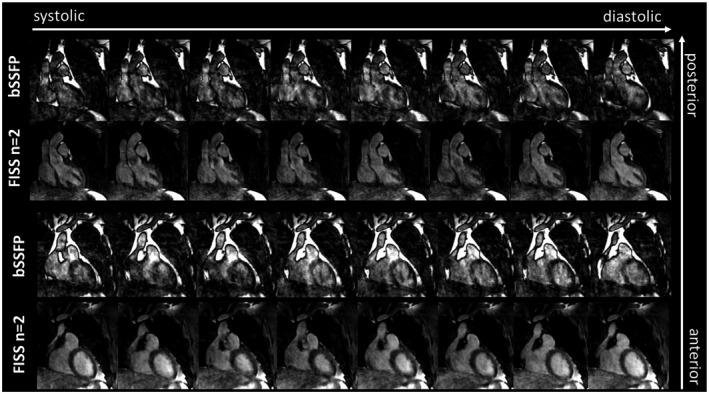

A periodic interruption of the balanced steady-state free precession (bSSFP) readout train (FISS) has been previously proposed for 2D radial imaging. FISS modulates the bSSFP frequency response pattern in terms of shape, width and location of stop band (attenuated transverse magnetization). Depending on the FISS interruption rate, the stop band characteristic can be exploited to suppress the fat spectrum at 3.5 ppm, thus yielding intrinsic fat suppression. For conventional 2D Cartesian sampling, ghosting/aliasing artifacts along phase-encoding direction have been reported. In this work, we propose to extend FISS to 3D Cartesian imaging and report countermeasures for the previously observed ghosting/aliasing artifacts. Key parameters (dummy prepulses, spatial resolution, and interruption rate) are investigated to optimize fat suppression and image quality. FISS behavior is examined using extended phase graph simulations to recommend parametrizations which are validated in phantom and in vivo measurements on a 1.5T MRI scanner for 3 applications: upper thigh angiography, abdominal imaging, and free-running 5D CINE.

Using optimized parameters, 3D Cartesian FISS provides homogeneous and consistent fat suppression for all 3 applications. In upper thigh angiography, vessel structures can be recovered in FISS that are obscured in bSSFP. Fat suppression in free-running cardiac CINE resulted in less fat-related motion aliasing and yielded better image quality.